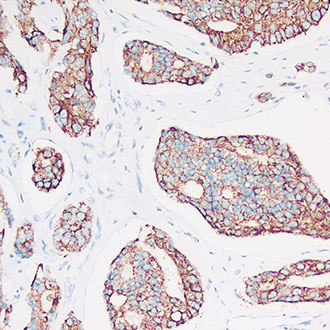

IHC

免疫组织化学(IHC)